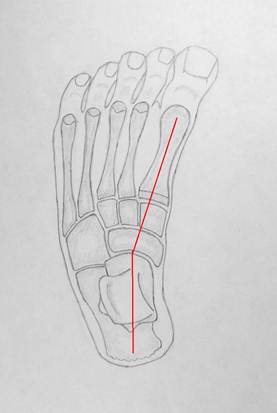

Варусная стопа

Вальгусная стопа

Красная

линия обозначает ось стопы в передне – задней проекции. Обратите внимание на

девиации в таранно – ладьевидном суставе, а также на то, как изменяется

взаимное расположение таранной и пяточной костей. В варусной стопе их длинные

оси почти параллельны, а в вальгусной они значительно расходятся. Подобные

взаимные перемещения есть результат работы сложной биомеханики стопы.